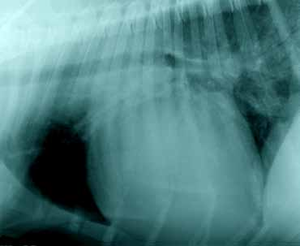

Radiología

El signo más característico es cardiomegalia derecha, especialmente el agrandamiento del atrio derecho con desviación del apex cardiaco hacia la izquierda.